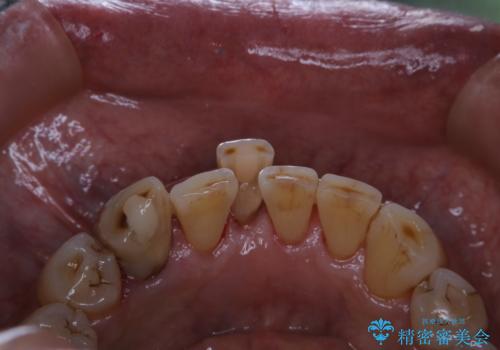

半年ぶりのクリーニング PMTC

- 半年、来院できなかったためきれいにクリーニングしたいとのことでした。久しぶりだったことと、全体的に汚れが付着していたためPMTC60分コースを行いました。

PMTCを行うとステインやバイオフィルム(細菌のかたまり)が除去され、ご自身本来の歯の状態になります。そのためスッキリとした爽快感が得られ、気持ちがいいです。また、口臭予防にもなります。

PMTCを継続的に繰り返していくうちに、歯の表面がつるつるになり虫歯や歯周病の予防につながります。継続して行うことが大切です。